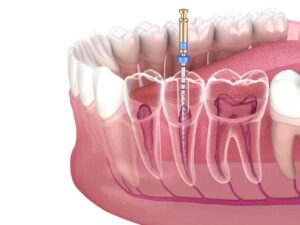

ويتكون السن من جزئين: التاج الذي يظهر فوق سطح اللثة والجذور التي تمتد في الفك. يتكون التاج من المينا الخارجية والتي تغطي التاج، بينما تغطي الجذور بطبقة الملاط. يتبع المينا والملاط طبقة العاج، وبعد ذلك يأتي لب السن الذي يحتوي على الأعصاب المسؤولة عن الإحساس والأوعية الدموية التي تغذي وتدعم السن.

خطوات سحب عصب الأسنان:

يتم إجراء سحب العصب على مراحل، ويشمل العديد من الخطوات:

- إزالة لب السن: يتم إزالة لب السن بعناية للتخلص من الأنسجة والأعصاب، ويمكن أن يشمل ذلك تصريف الخراج إذا كان موجودًا.

- تنظيف اللب وملء قناة الجذر: يتم تنظيف تجويف اللب وتطهيره للتأكد من خلوه من البكتيريا، ثم يتم ملء قنوات الجذر استعدادًا للمرحلة التالية.

- غلق قناة الجذر وحشو السن: يتم إغلاق قنوات الجذر بمادة خاصة لمنع التسرب وحشوها بشكل كامل، ثم يتم وضع حشوة لإغلاق السن.